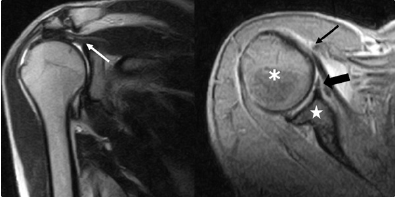

The patient was a 56 years old male, who felt down on the floor with the arms thrown back in July 2019 (Table 3). During this event he also smacked his head against a table, suffering head trauma. In following months, he developed right shoulder pain and, in January of 2020, he was referred by his Physician (D.M.) to an orthopaedic surgeon (D.L., M.P.). MRI revealed a massive rupture of rotator cuff and the patient was scheduled to undergo arthroscopy on March 2020 for primary repair (Figure 7). However, due to Covid-19 restrictions in that period, surgery was postponed until June of 2020. and then was further delayed because patient was afraid to be infected by Covid-19 in hospital. Patient withdrew also from rehabilitation treatment for the same reason. An MRI carried out in December of 2020 revealed a total rupture of tendon of the long head of the biceps brachii and limited range of motion of the right shoulder (photos taken and sent to Physician by patient’s son, Figure 8).

Figure 7: Signs of lesions on MRI; white arrow: supraspinatus tendon lesion; asterisk: humeral head; star: scapula; small black arrow: subscapular tendon lesion; fat black arrow: anterior glenoid labbrum lesion.